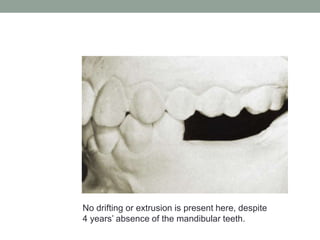

No drifting or extrusion is present here, despite

4 years’ absence of the mandibular teeth.

No drifting orextrusion is present here, despite 4 years’ absence of the mandibular teeth.